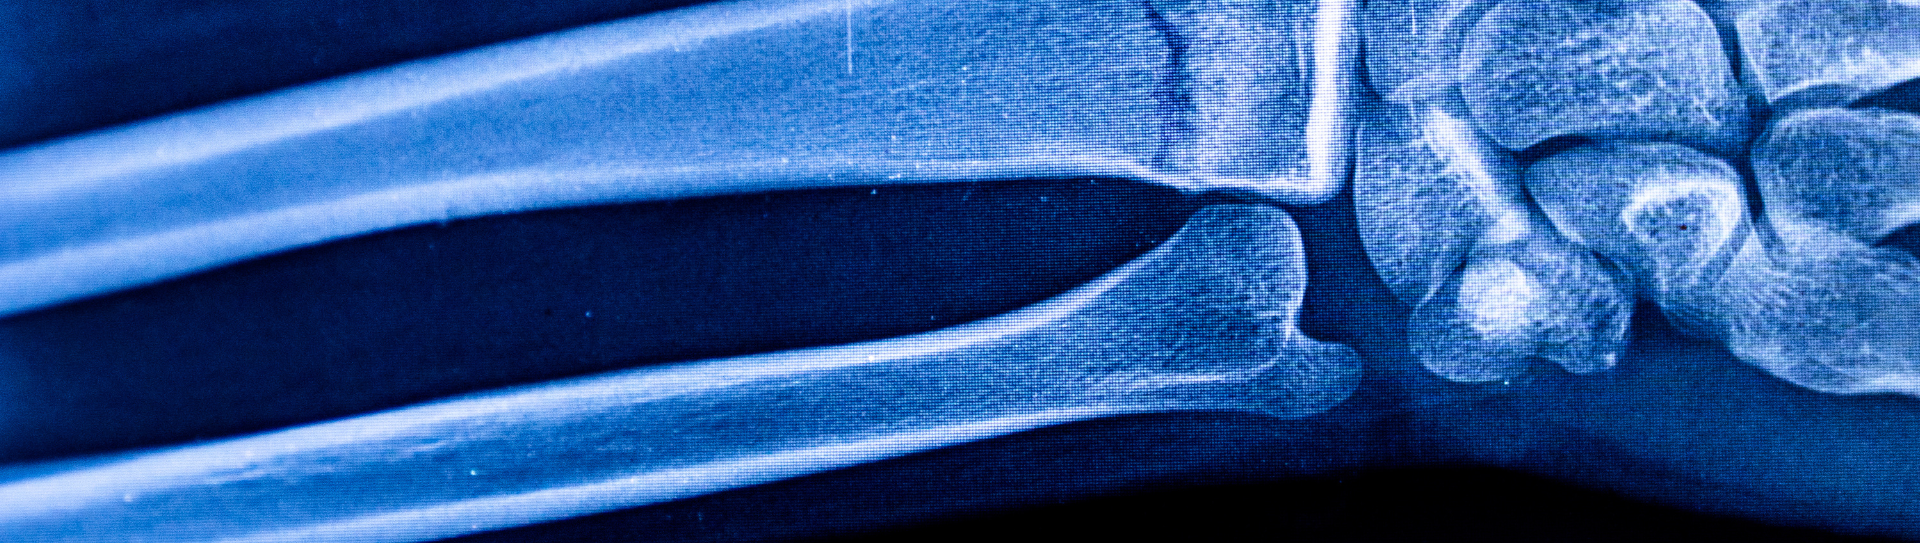

L’Esame RX Avambraccio è una procedura radiografica che utilizza i raggi X per ottenere immagini dettagliate dell’ulna e del radio, le due principali ossa dell’avambraccio. Questo tipo di esame è particolarmente indicato per identificare fratture, lussazioni e altre alterazioni delle strutture ossee e dei tessuti molli circostanti. Grazie alla sua capacità di fornire immagini ad alta risoluzione, l’RX Avambraccio è uno strumento essenziale per il monitoraggio e la diagnosi di molte patologie.

Grazie all’Esame RX Avambraccio, i medici possono ottenere immagini chiare e dettagliate dell’intera struttura ossea dell’avambraccio, inclusi radio e ulna. È possibile visualizzare:

• Fratture recenti e pregresse.

• Microfratture non visibili con altri strumenti diagnostici.

• Lussazioni articolari o instabilità dell’avambraccio.

• Anomalie strutturali come lesioni ossee o calcificazioni.